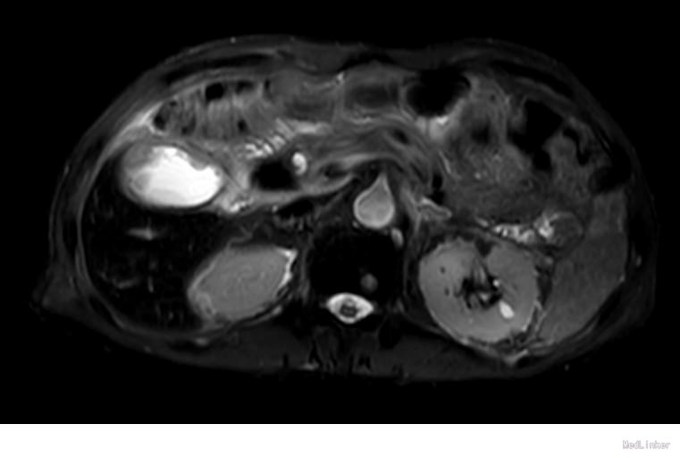

查体:右上腹轻压痛,无反跳痛、肌紧张。墨菲氏征弱阳性。 辅助检查:腹部CT:胆囊体积增大,壁增厚,以胆囊底部为著,增强扫描可见轻度强化,胆囊周围可见积液。MRI:胆囊增大,壁增厚,壁内可见多发结节状低信号灶。胆囊内可见泥沙样短T2信号影。